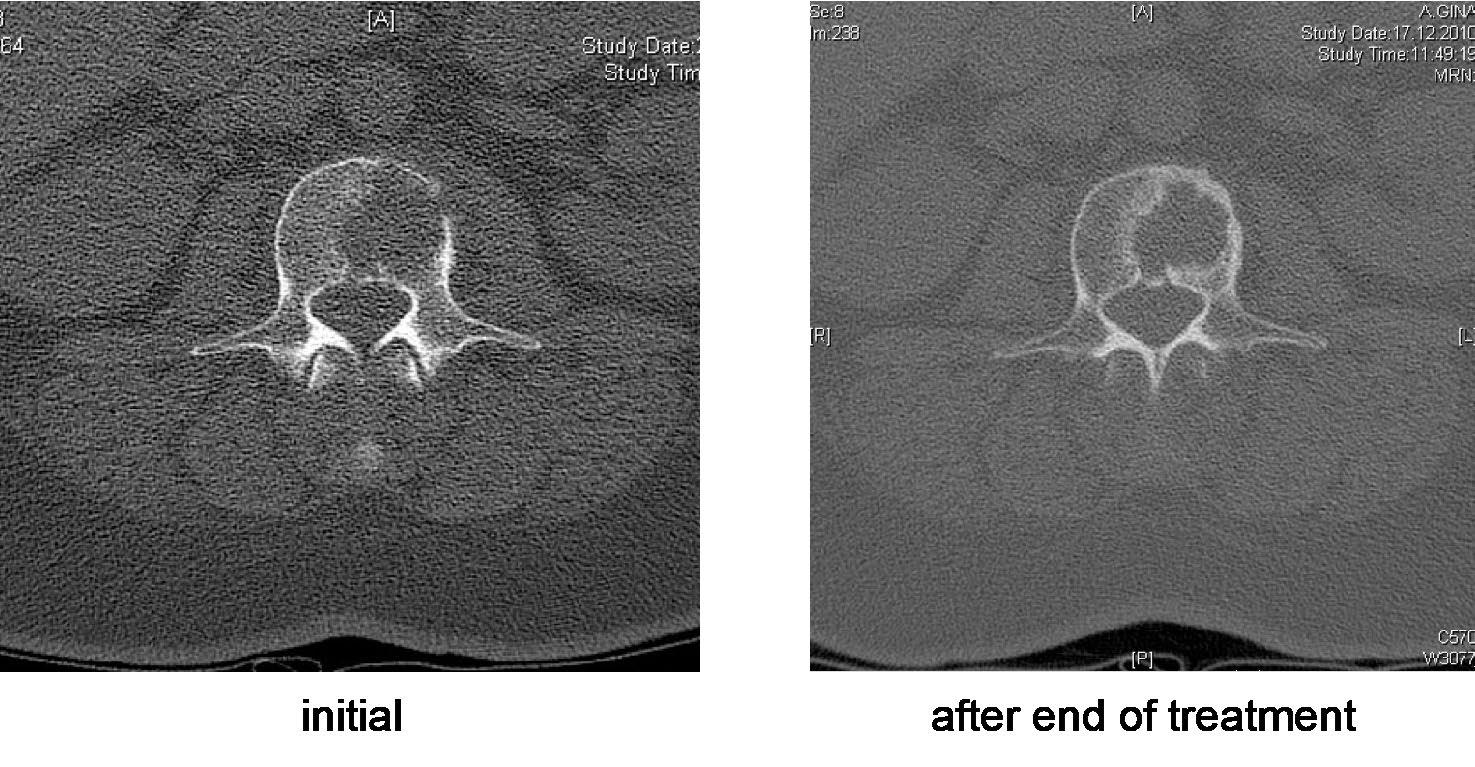

Myeloma Bone Disease

Merz 2022 Nature Comm

Saad 2007 Cancer, Melton 2005 J Miner Res